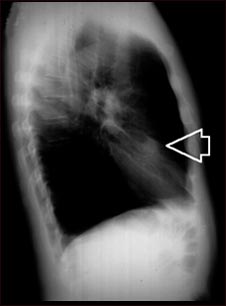

Nódulo pulmonar, lóbulo medio derecho- Radiografía de tórax

Esta es una radiografía de tórax (RXT) de un nódulo en el pulmón derecho.